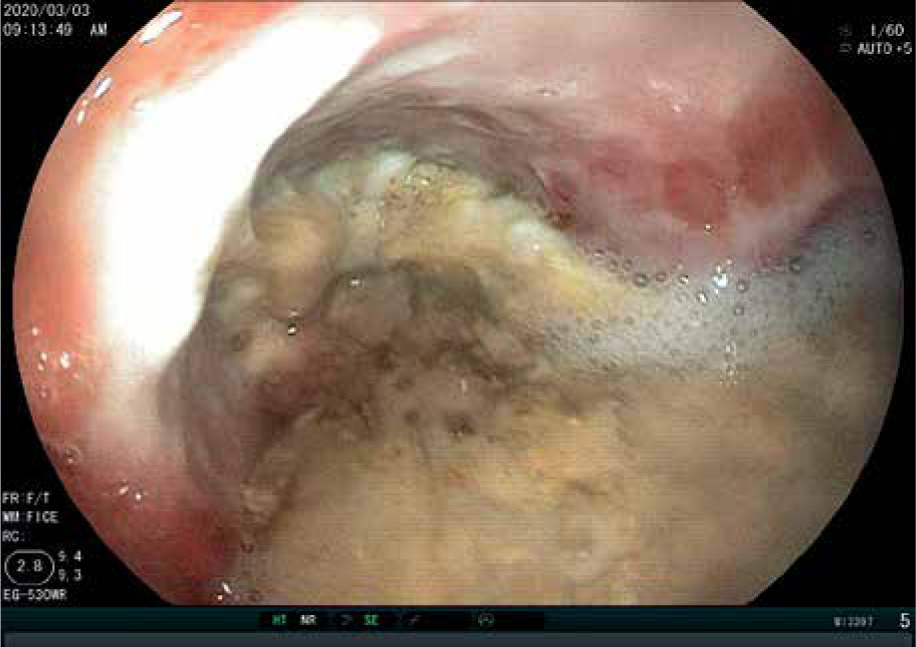

Figure 2

Endoscopic finding of stomach in female after ingestion of hydrochloric acid ingestion (grade III)